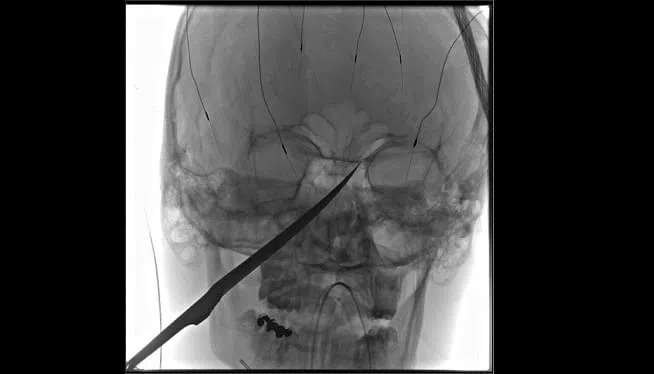

KANSAS CITY, Kan. — A 15-year-old Kansas boy got a large knife to the face, and doctors say he’s extremely lucky.

Jimmy Russell said her son, Eli Gregg, was playing Thursday evening outside of their home in Redfield, about 90 miles (145 kilometers) south of Kansas City, when she heard him scream. She found him with a 10-inch knife jutting from just below his eye and called 911.

The knife was embedded in his skull and extended to just under his brain. The blade’s tip, meanwhile, was pushing against his carotid artery, which supplies the brain with blood.

“It could not have had a pound more force on it and him survive that event,” said Dr. Koji Ebersole, who oversaw the extraction. “I don’t think he would have survived it.”

A team of surgeons put together an intricate plan to remove the blade Friday morning. They were prepared for possible bleeding into the brain, but the operation went without a hitch and the artery remained intact.